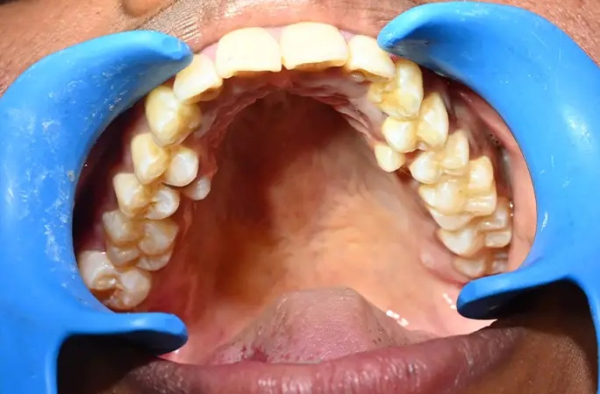

У девушки на шесть зубов больше, чем у большинства людей: у жительницы Индии насчитали 38 зубов вместо 32-ух. При этом у неё нашли ещё два зуба, которые не прорезались. Больше только у мужчины из Канады — 41 штука.